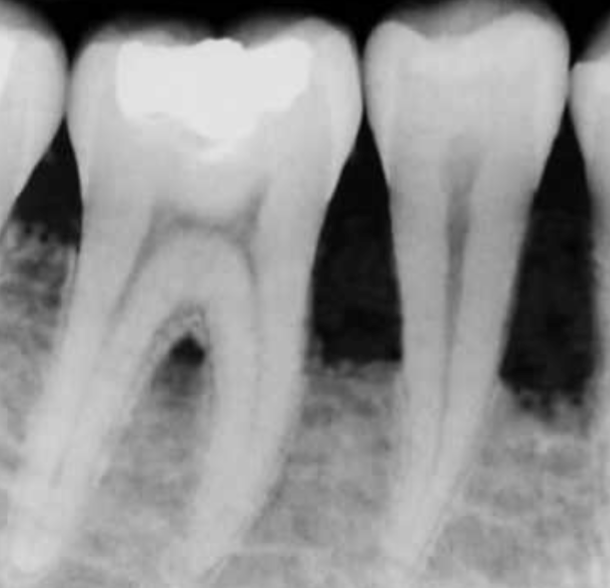

<p>Microscopic Anatomy of Cementum:</p>

Microscopic Anatomy of Cementum:

• mineralized tissue covering tooth roots

• periodontal ligament fibers embed in cementum to attach tooth to bone

• involved in tooth repair and generation

• seals open dentinal tubules

• continues to grow in thickness as we age, to compensate for occlusal/incisal attrition

<p>Cementum Conservation when Instrumenting:</p>

Cementum Conservation when Instrumenting:

• instrumentation can lead to exposure of dentin, causing hypersensitivity

• cementum removal is not necessary to eliminate bacteria

• preservation of cementum is important because of its source for growth factors

<p>Three Types of Cementum:</p>

Three Types of Cementum:

• Intermediate-located at CEJ

• Acellular-composed mainly of Sharpey Fibers, contains no living cells

• Cellular-contains cementocytes and fibroblasts

• present at apical and interradicular parts of root